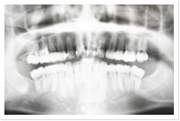

歯の大きさが極端に大きく、いずれ抜歯が必要となるケースであっても、小児期であればあごの成長をバランスよくコントロールできるので、歯並び矯正がより良く仕上がります。

乳歯の抜歯タイミングをコントロールする事により、悪い方向に生える原因を減少させ、かみ合わせを良い状態に導きます。

あごの成長期において、かみ合わせが正しくない状態を放置すると、よりあごの変形を悪化させることがあります。

あごの成長が残っている時期にかみ合わせを改善してあげる事で、バランスのとれた偏りの無いかみ合わせに改善できる可能性も十分あります。

歯の生え変わりの時期に、歯の傾きが原因で受け口になっている場合、そのまま放置すると、悪い傾きの歯にそって顎が成長してしまいます。そして成長が止まる頃には顎のずれが大きくなりすぎて、改善するには顎の手術を併用した矯正治療が必要となることがあります。

しかし、あらかじめ、かみ合わせを治す事により、かみ合わせのバランスのとれた顎の成長が起こり、手術の必要性が減少します。

狭かったあごを広げたり、あごの成長を正しい形に促したりする事で、不必要な抜歯の可能性を減らす事ができます。

例えば成長後に矯正治療をした場合、2~4本の永久歯抜歯が必要な場合でも、小児期から矯正治療を行う事により、非抜歯での治療が可能になる確率が高くなります。